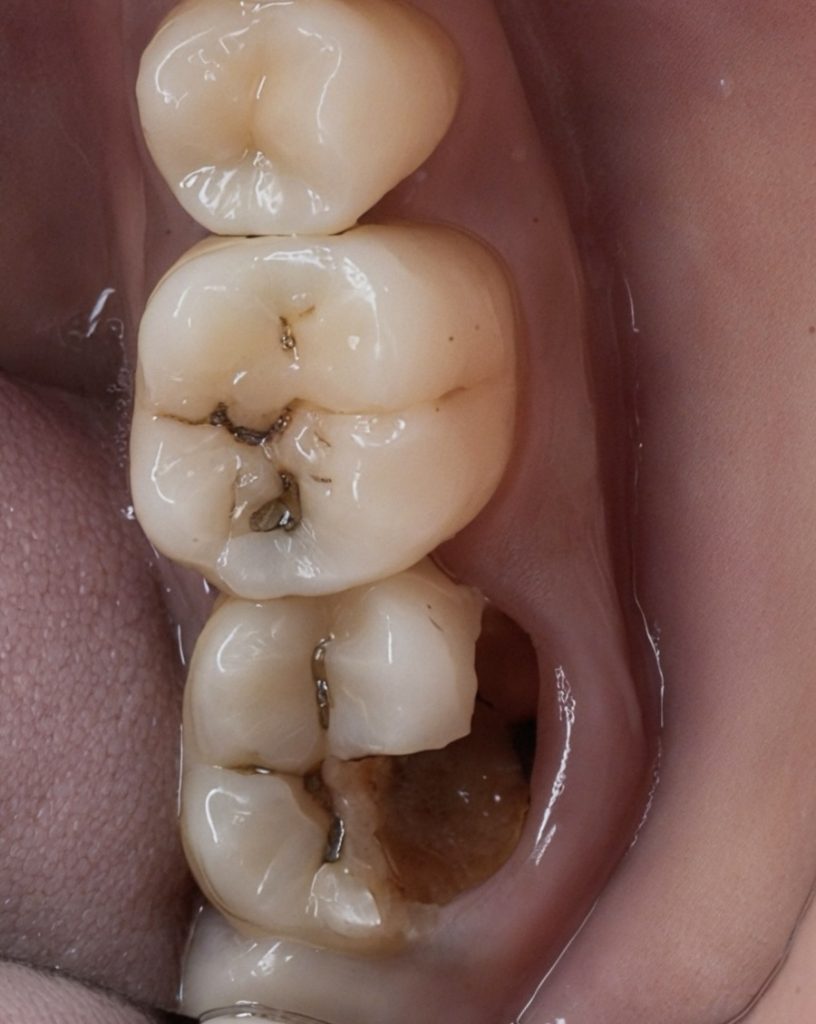

1 Pre-operative Assessment

Clinical and radiographic evaluation showed a large Class V lesion extending below the CEJ with pulpal involvement and secondary dentin sclerosis (Fig 1 & 2).

1️⃣ Pre-operative view showing deep Class V caries